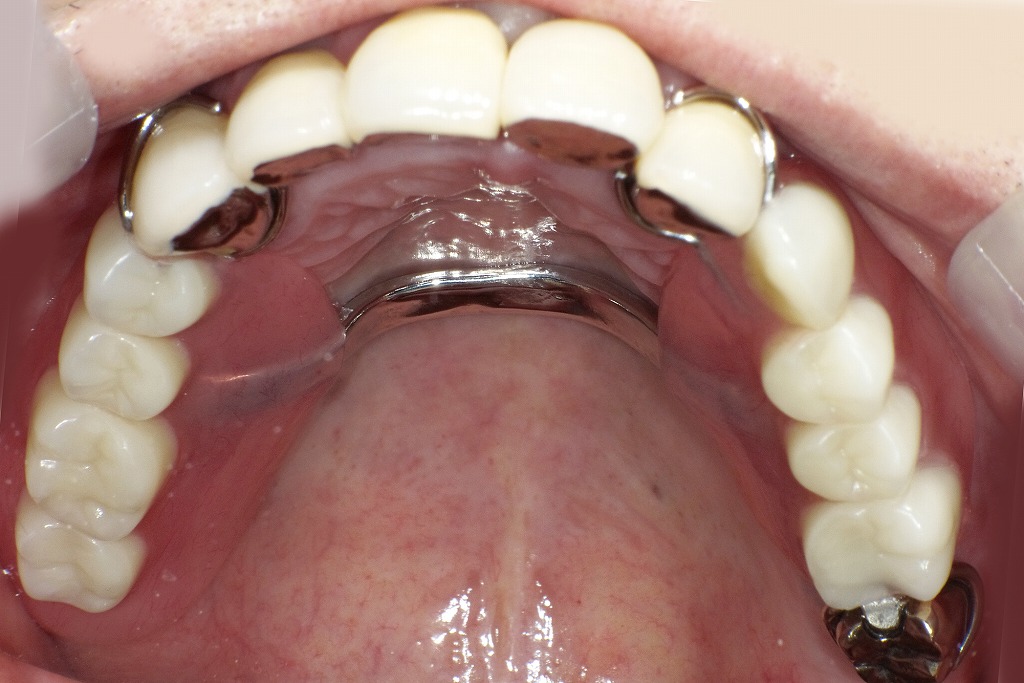

最終補綴治療(硬質レジン前装冠+保険義歯)

この画像は、**上顎咬合面観(最終補綴後)であり、保険適用の義歯(レジン床+パラタルバー)**が装着された状態を示しています。

前歯部・臼歯部ともに機能的・審美的に回復しており、治療の最終段階を反映しています。

🦷 全体的な構成

- 前歯部:硬質レジン前装冠(保険)

- 義歯構造:パラタルバー(口蓋バー)

- 維持装置:保険の金属クラスプ(ワイヤークラスプ)

🔍 各部の詳細解説

① 前歯部(硬質レジン前装冠)

- 前歯部(右上3番〜左上2番)にかけて硬質レジン前装冠が装着。

- 金属裏打ちの上にレジンを築盛しており、自然な色調と形態を再現。

- 保険適用範囲内でありながら、審美性と咬合強度のバランスが良い。

- 仮歯の段階で確立した咬合・発音・見た目をそのまま最終補綴に反映。

② パラタルバー(口蓋バー)

- 義歯の中央部に金属製のパラタルバーが設けられており、左右を連結。

- 構造的強度を高め、咬合力を均等に分散。

- 発音障害や違和感を最小限にするため、厚み・位置ともに適切に設計されている。

③ クラスプ(維持装置)

- 残存歯に金属クラスプが設けられ、義歯の維持と安定を確保。

- 保険診療で一般的な**ワイヤークラスプ**を使用。

- クラスプの形状は歯面に沿って滑らかで、審美性と清掃性に配慮されている。

🩺 臨床的評価

- 前歯部の審美回復、臼歯部の咬合支持、義歯の安定性が良好。

- 残存歯の支台構造を活かしつつ、全顎的な咬合再構成が達成されている。

- 金属構造(パラタルバー)により、変形の少ない強固な補綴設計。

- 義歯床の辺縁適合も良好で、舌感・発音・咀嚼効率に優れた状態。